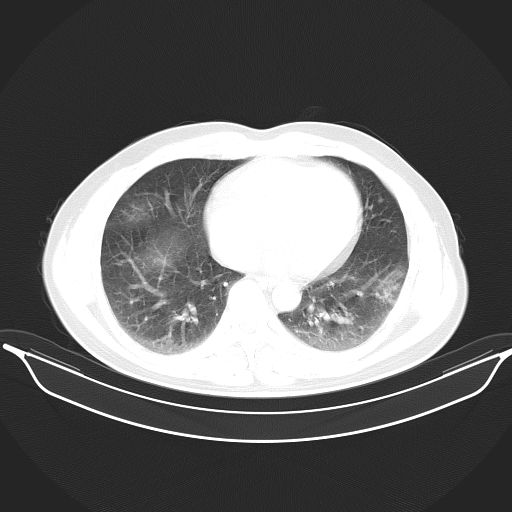

标题: CT25490:男,40岁,体检发现;无其它不适。 [打印本页]

标题: CT25490:男,40岁,体检发现;无其它不适。

倾向于结核

多考虑结核。

考虑结核

考虑肺霉菌病。

没有结核的诊断依据。

考虑右下肺周围性肺癌并肺内多发转移,纵隔淋巴结转移!

考虑过敏性肺炎,建议抗炎后复查,转移瘤及tb待排

支持 !考虑右下肺周围性肺癌并肺内多发转移,纵隔淋巴结转移,(气管前腔静脉后,隆突下,主动脉弓下都有了)